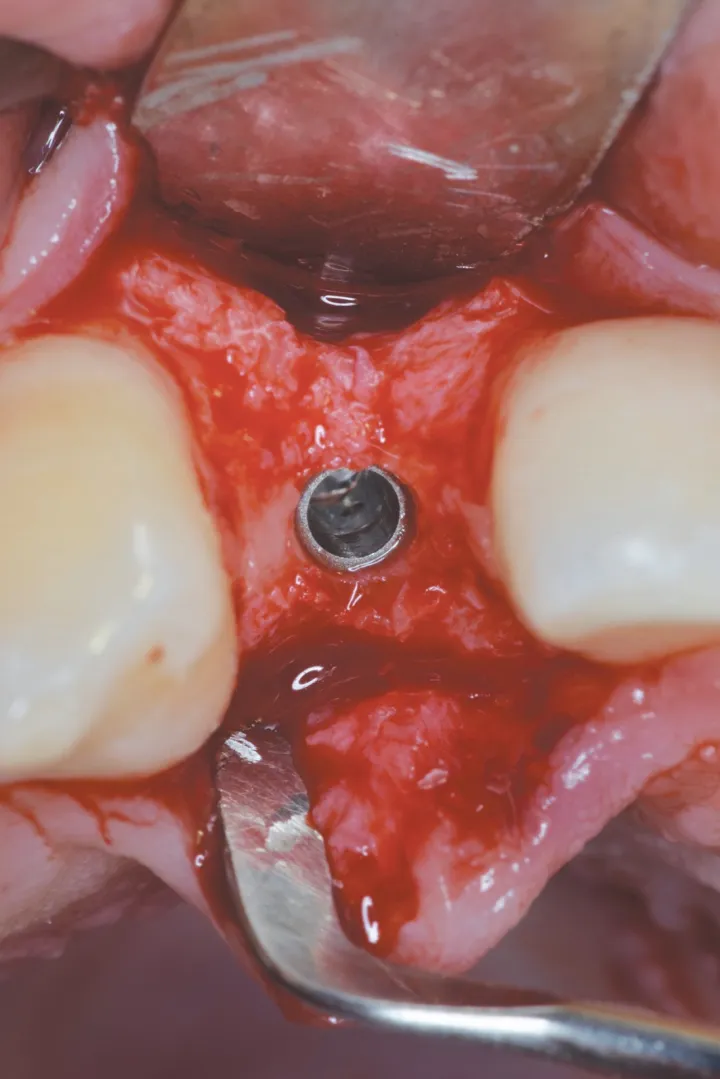

2 号病例 - Patrick EXBRAYAT 医生(图 21 至 35)

22 岁患者,23 异位,行正颌外科种植术后 22 出现严重根吸收。

图 24 :植入 Axiom® 2.8 x 14 种植体。

图 25 :种植体就位。

图 38 :拔牙后种植位点。